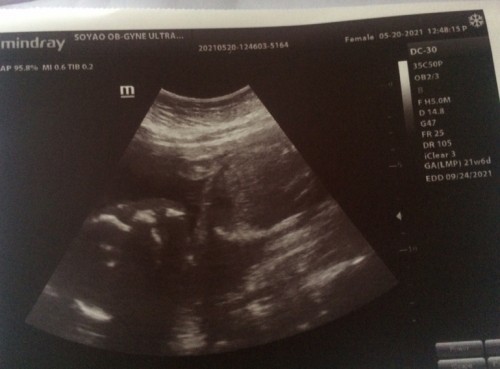

#firstbaby #pleasehelp Hi mga mommy, 26 weeks na ako ngayon . Noong around 22 to 24 weeks ay panay ang galaw ni baby. Tapos ngayong nag 26 na siya, medyo dumalang yung pag galaw niya, normal lang po ba yon? Noong 24 weeks ramdam ko ang galaw ng mga paa niya, ngayon dumalang yung galaw niya, yung parang pitik nalang di ko na ma feel mga paa niya, di na siya masyado makulit. #firstbaby #pleasehelp #pasagotpo #pasagotposamayalamthanks Ultrasound ko noong 5months pa lang dipa define yung gender .